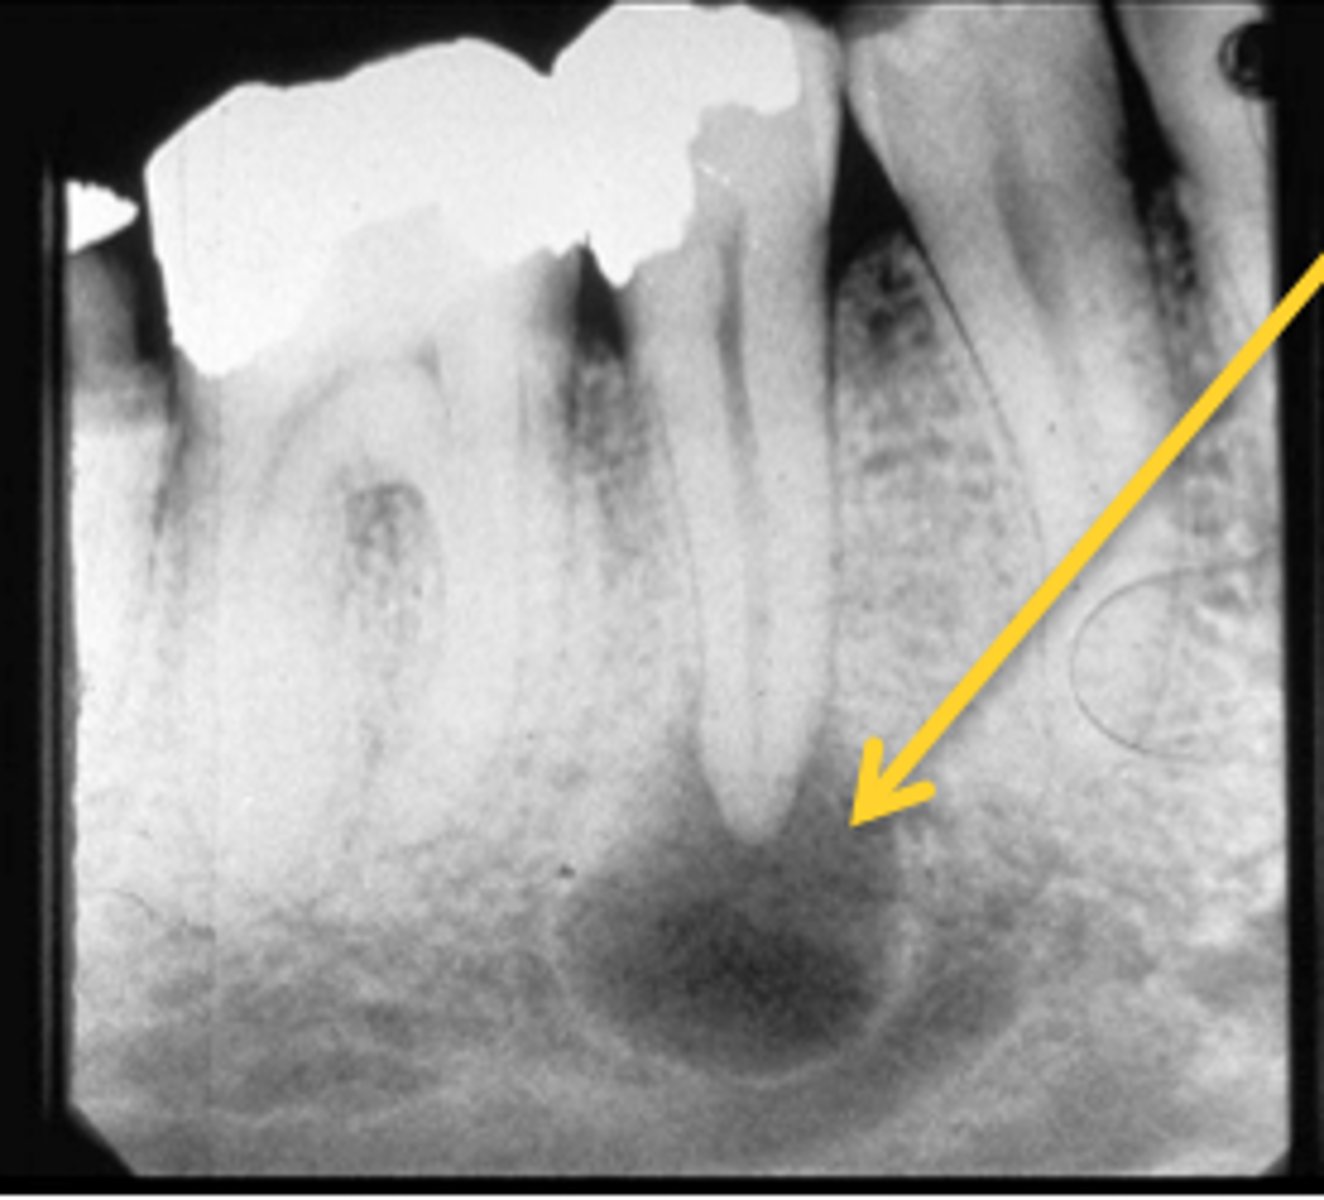

Where are radicular cysts found?

Apex of tooth

What type of teeth are associated with radicular cysts?

Nonvital teeth

What is the most common cyst?

Radicular cyst

How is a radicular cyst described radiographically?

Well corticated

What is the treatment for radicular cysts?

Enucleation